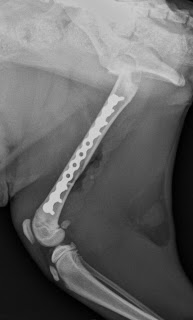

Gatto femmina di 4 mesi di 1,8 kg.

Frattura di femore SPIROIDE diafisaria con una piccola scheggia.

Rididuzione con placca lcp synthes del 1.5mm applicata lateralmente evitando di ingaggiare le fisi di accrescimento dell'epifisi prossimale e distale.